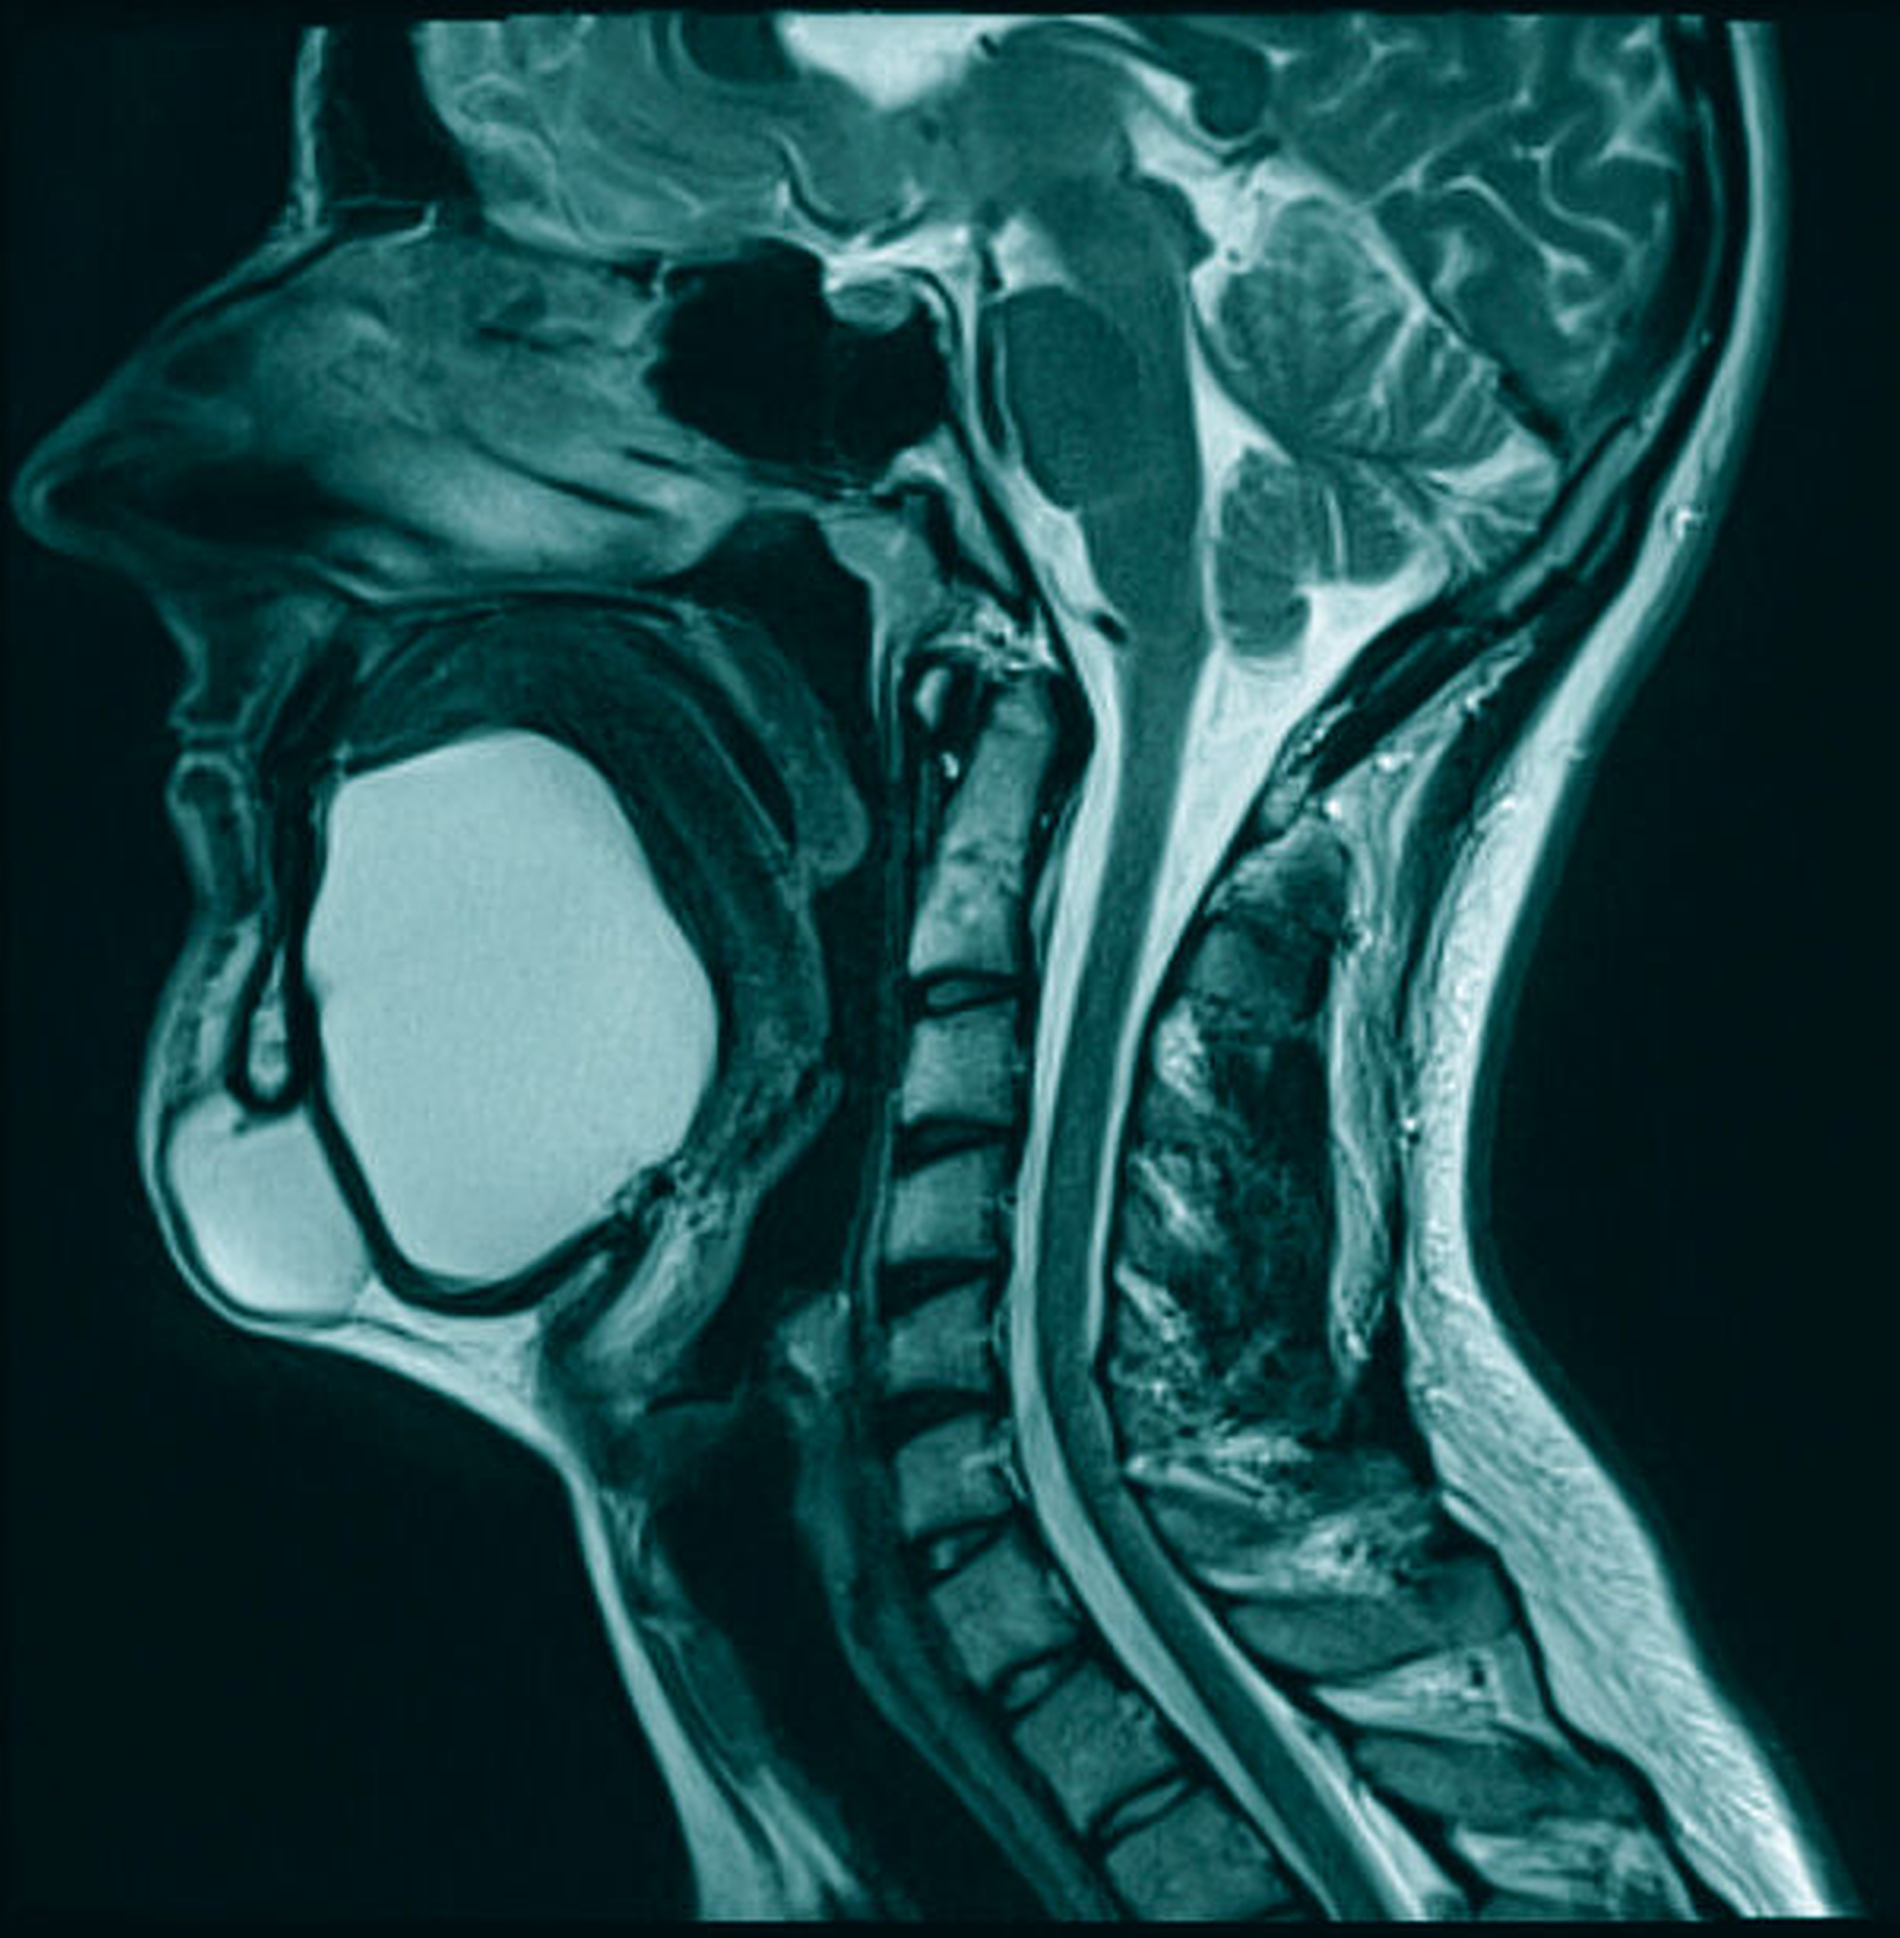

Zur Diagnostik erfolgten eine Sonografie sowie eine Magnetresonanztomografie des Halses. Hierbei kamen zwei voneinander getrennte zystische Raumforderungen submental und im Bereich des Mundbodens zur Darstellung: Die submentale Raumforderung mit einer Größe von maximal 3,5 cm war direkt zwischen der Hautoberfläche und dem M. mylohyoideus, dem Unterkieferknochen angrenzend, lokalisiert. Die zweite Raumforderung mit einer Größe von 6,5 cm erstreckte sich großflächig entlang des gesamten Mundbodens, oberhalb des M. mylohyoideus, mit resultierender Verdrängung der tiefen Zungenmuskulatur und des Zungenkörpers sowie direkter Nachbarschaft zum Ausführungsgang und der Glandula submandibularis beidseitig und ohne Kontakt zum Zungenbein (Abbildungen 3 bis 5).